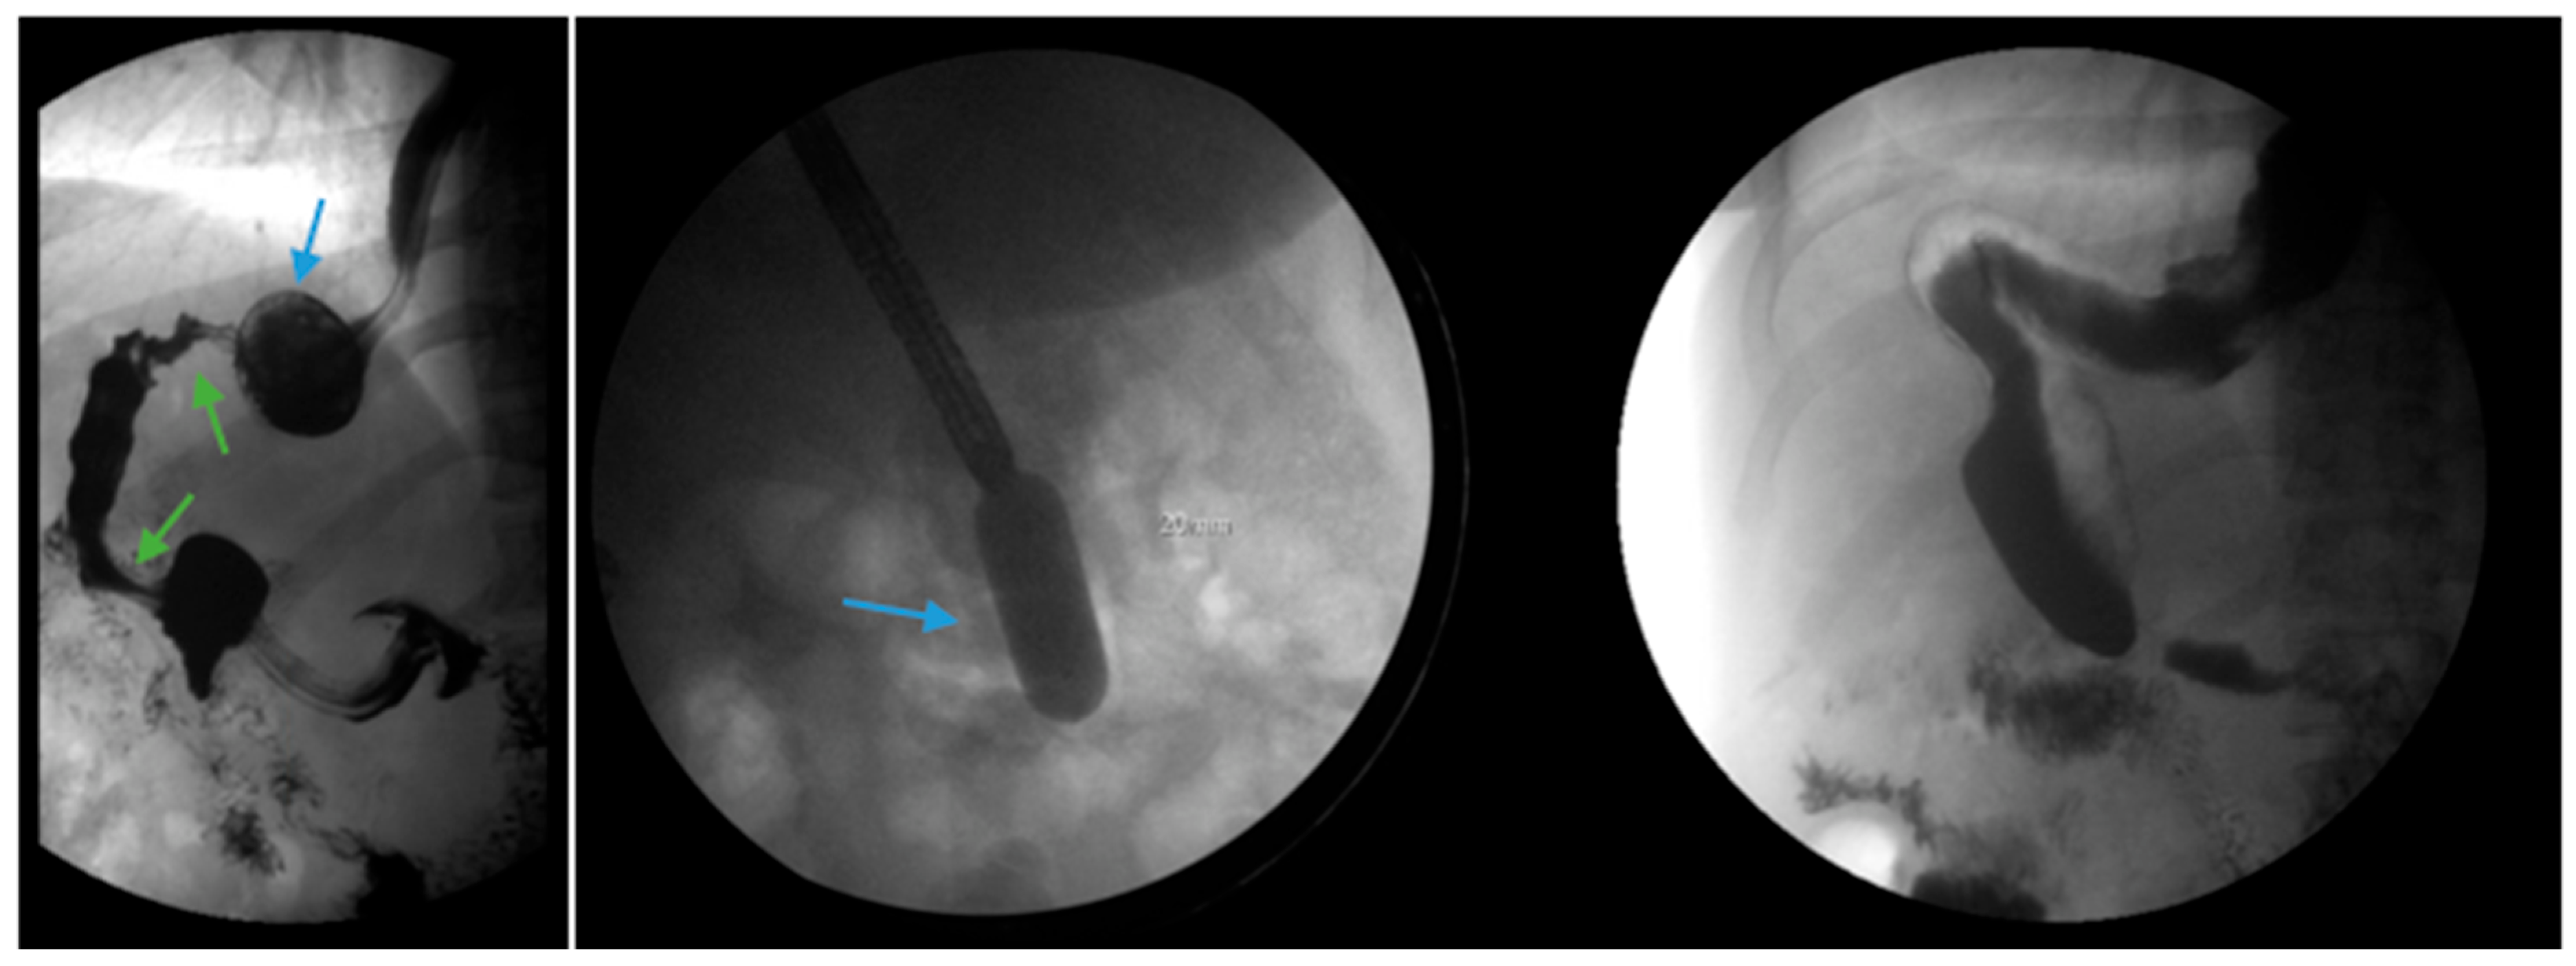

Conversion from SG to RYGB is ultimately necessary for some patients with refractory GERD post-SG (Figure 6). There are robust data that conversion to RYGB is very effective for the treatment of GERD, as detailed in Table 2, in addition to its beneficial effects on weight loss and other comorbidities (i.e., diabetes, hypertension, dyslipidemia). In a recent retrospective study by MacVicar et al., 4412 patients required revisional surgery due to GERD, which comprises 24% of all conversion procedures [71]. SG was the original surgery in 80.1% of cases and Roux-en-Y was the revisional surgery in 84.4% of cases [71]. However, conversion from SG to RYGB is not without additional risk. In a recent study with matched cohorts of 5912 patients, an increase in re-admissions, intervention, conversion to open surgery and operative time was documented in the group which underwent conversion from SG to RYGB compared to primary RYGB. There were no significant differences in mortality or complications noted between the two groups. In a study by Dang et al., conversion from SG to RYGB compared to primary RYGB was associated with an increased rate of serious complications (7.2% vs. 5%, p < 0.001), including anastomotic leaks, bleeding and reoperation, although no significant difference in mortality between the two groups was demonstrated in the study [72].

Figure 6.

Endoscopic images reveal a 3 cm hiatal hernia (arrows, top left) and Los Angeles Grade B esophagitis (arrows, top right) in the lower third of the esophagus with narrow-band imaging in a patient post-sleeve gastrectomy with symptoms of gastroesophageal reflux disease. The patient eventually required Roux-en-Y gastric bypass (arrow, bottom) and concomitant hiatal hernia repair, as demonstrated on upper gastrointestinal series.

Due to the prevalence of hiatal hernias in the bariatric population, several studies have explored GERD outcomes when SG is combined with either fundoplication or hiatal hernia repair (Figure 7 and Figure 8) [82,83,84,85,86,87,88,89,90,91,92,93,94]. The authors acknowledge that the published studies on SG combined with either fundoplication or hiatal hernia repair are investigational, with a limited sample size and variable follow-up. We summarize the published data regarding SG combined with either fundoplication or hiatal hernia repair to highlight experimental approaches to GERD post-SG beyond conversion to RYGB with hiatal hernia repair.

Figure 7.

An upper gastrointestinal series reveals a small, sliding hiatal hernia (bottom arrow) in addition to gastroesophageal reflux disease (top arrow) in a patient following sleeve gastrectomy.

Figure 8.

An upper gastrointestinal series reveals a small, sliding hiatal hernia (bottom arrow) with spontaneous gastroesophageal reflux (top arrow) in a patient following sleeve gastrectomy.